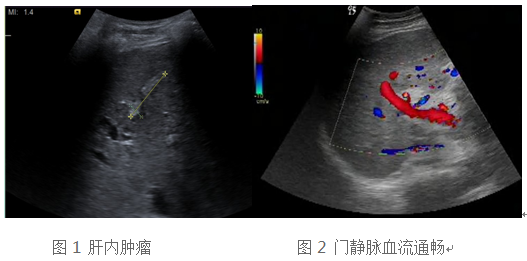

59岁的肝硬化肝癌患者白先生,入住我院移植科,准备肝移植手术,术前完成相关组织配型及手术风险评估,患者及移植团队专家担心的是,是否有癌肿肝外转移,心脏扩大能否耐受手术。通过全面系统的超声检查,我们得出的结论是虽然患者肝内有肝癌占位(图1),但是肝外脏器及门静脉内部未见转移(图2),根据欧洲肝病协会(EASL)发布的《2015 年肝移植临床实践指南》,属于肝移植手术的适应症。患者超声心动图提示左心室及左心房扩大,但是心脏收缩功能尚正常,所以能耐受肝移植手术。